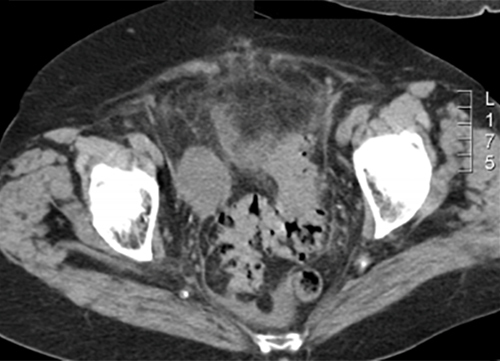

Le diagnostic est tout à fait possible, à évoquer ici en première intention devant l’âge (> 40 ans) et la symptomatologie (douleurs fébriles en fosse iliaque gauche et hypogastre).

– de la localisation de la douleur en fosse iliaque gauche ;

– du syndrome inflammatoire : fièvre à 38,5 °C avec hyperleucocytose à la biologie ;

– de l’argument de fréquence de cette pathologie à cet âge (la prévalence des diverticules sigmoïdiens est de plus en plus importante avec l’âge, après 40 ans).